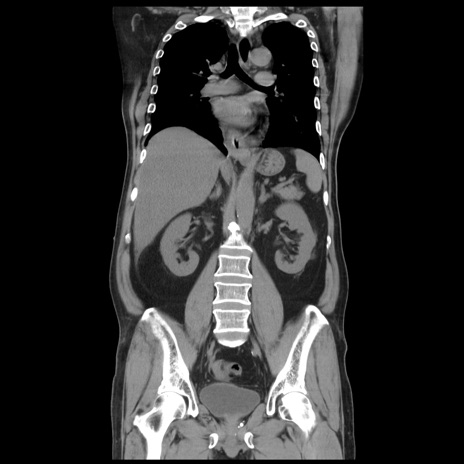

症例20(冠状断像)

【症例】 60歳代男性

【主訴】 腹部膨満、嘔吐

【現病歴】5日前頃より倦怠感を認め食事量減少し4日前の朝嘔吐、食事摂取困難となった。 3日前近医受診し点滴施行され整腸剤などを処方された。 当日他院を受診し、腹部膨満著明、炎症反応の上昇(CRP10.8、WBC11200)あり、紹介受診となる。

【身体所見】 意識JCS1 受け答えがはっきりしないBP 111/57mHg、 P 67bpm、、BT35.2°C、SpO2 97%(RA)、 腹部:膨隆、打診で鼓音あり、全体的に圧痛有り、腸蠕動音(-)、反跳痛ははっきりせず。

【データ】WBC 11400、CRP 14.20